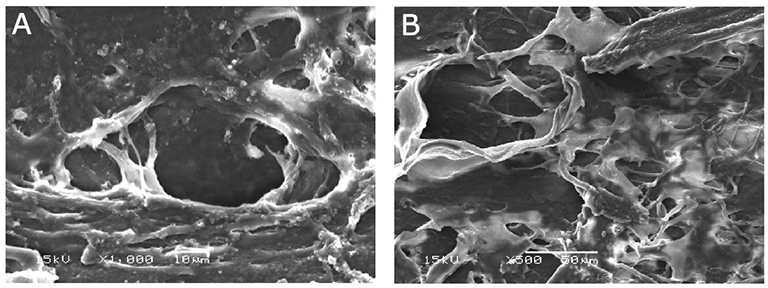

2. 섬유주소대(Trabecular meshwork, TM)의 직접적인 변화로,

레이저를 받으면 TM에 있는 내피세포가 소실되고 손상이 되면,

그 찌꺼기를 제거하려는 대식세포(Macrophage)의 기능이 증가되면서,

내부의 찌꺼기가 제거되면서 TM 내부의 공간이 넓어지면서 방수유출이 증가됩니다.